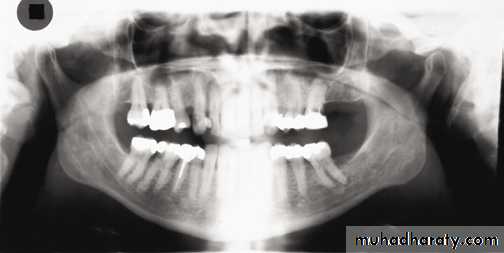

The normal anatomical shadows can be subdivided into:True or actual image of structures in, or close to the focal trough.

Ghost images created by the tomographic movement and cast by structures on the opposite side or a long way from the focal trough. The 8° upward angulation of these ghost shadows appear at a higher level than the structures that have caused them.

Double images: structures that are scanned twice by the rotating X-ray beam.

Important hard tissue images):)True or actual images

These include:• Teeth.

• Mandible.

• Maxilla, including the floor, medial and posterior walls of the antra.

• Hard palate.

• Zygomatic arches.

• Styloid processes.

• Hyoid bone.

• Nasal septum and conchae.

• Orbital rim.

• Base of skull.

Air images

• Mouth/oral opening

• Oropharynx.

Important soft tissue images

• Ear lobes

• Nasal cartilages

• Soft palate

• Dorsum of tongue

• Lips and cheeks

• Nasolabial folds.

Ghost images

:The more important ghost shadows

• Cervical vertebrae.

• Body, angle and ramus of the contralateral side

of the mandible

• Palate.

Double images

( hyoid bone, the hard palate, epiglottis).A dental panoramic tomograph showing the main real hard tissue shadows, including the plastic head support, drawn in on one side of the radiograph, NS — nasal septum,

MIT — middle and inferior turbinates, O — orbital margin, HP — hard palate, A — floor of antrum, Z — zygomatic arch, EAM — external auditory meatus, MP — mastoid process,

SP — styloid process, H — hyoid, P — plastic head support.

A dental panoramic tomograph showing the main real soft tissue and air shadows drawn in on

one side of the radiograph, NC — nasal cartilages, EL — ear lobe, SP — soft palate,DT — dorsum of tongue, Or — oropharnyx, NF — naso-labial fold, M — mouth.

A dental panoramic tomograph showing the main anatomical ghost or artefactual shadows drawn in on one side of the radiograph, PI — palate, Md — mandible, CV — cervical vertebrae.